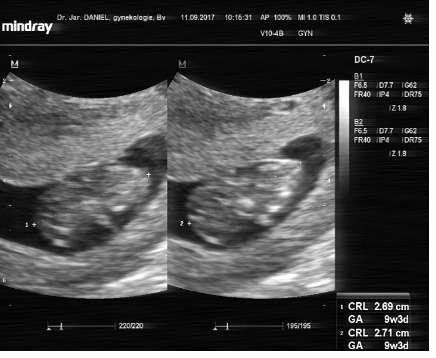

Vcerejsi screening dopadl na vybornou, cekame zdravou krasnou holcicku 💕😍😘